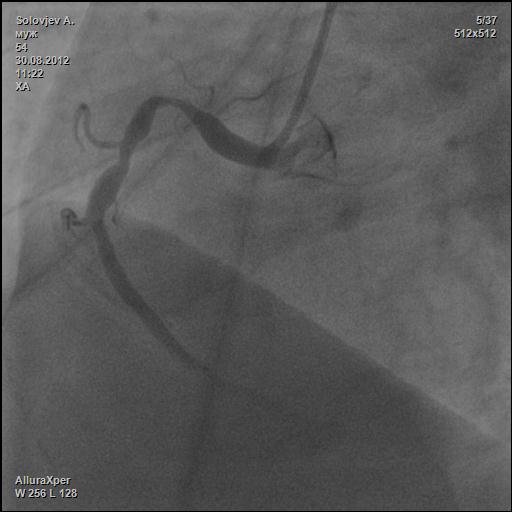

М. 54г. Ел пил все подряд. Лечили подагру, когда прижмет. Курил сигаретки. И вот тебе сюрприз.

Ваш диагноз? Как лечить?

КАГ.jpg

КАГ.jpg [ 26.53 KiB | Просмотров: 27907 ]